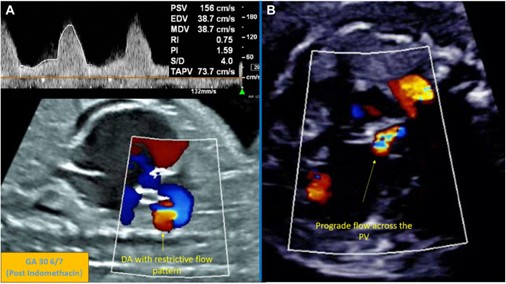

The latest issue of CASE is now available with intriguing reports, including “Indomethacin-Induced Ductus Arteriosus Closure and Aortopulmonary Collateral Formation in Fetal Ebstein Anomaly With Circular Shunt by Rao et al. These authors remarked, “Our report highlights the careful balance of benefit and risk when using transplacental indomethacin in fetuses with severe Ebstein

anomaly and circular shunt physiology. While therapy may improve hemodynamics, it also carries the potential for irreversible ductal closure with important implications for pulmonary vascular development and postnatal surgical planning. This case also demonstrates how serial fetal echocardiography can guide timely intervention and individualized management in a critically ill fetus.”